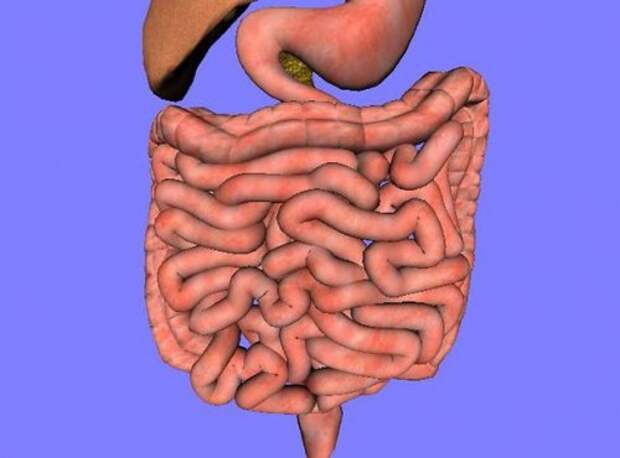

24. Длина тонкой кишки – примерно 6,7 метра, а длина толстой – около 1,8 метра.

Фото: LearnAnatomy

21. Тонкая кишка человека состоит из трех отделов – из двенадцатиперстной кишки, тощей кишки и подвздошной кишки.

Фото: BruceBlaus

19. Вопреки распространенному мнению, большая часть пищеварительных процессов протекает именно в тонкой кишке, а не в желудке.

Фото: Arnavaz / French Wikipedia, Medium69

24. Длина тонкой кишки – примерно 6,7 метра, а длина толстой – около 1,8 метра.

Фото: LearnAnatomy

21. Тонкая кишка человека состоит из трех отделов – из двенадцатиперстной кишки, тощей кишки и подвздошной кишки.

Фото: BruceBlaus

19. Вопреки распространенному мнению, большая часть пищеварительных процессов протекает именно в тонкой кишке, а не в желудке.

Фото: Arnavaz / French Wikipedia, Medium69